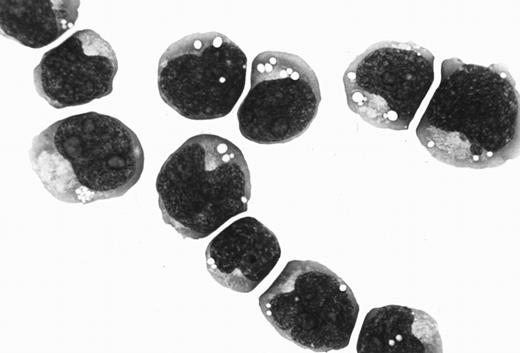

Morphology, phenotype, and genotype.The Katata line was predominantly composed of medium-sized cells with round or slightly irregular nuclei and one or more prominent nucleoli. The cytoplasm was basophilic and contained prominent vacuoles (Fig 2). The morphology of Katata cells closely resembled the original lymphoma cells. The results of cell marker analysis of the patient's lymphoma cells and cell line are summarized in Table 1. Both original lymphoma cells and cell line displayed an immunophenotype of immature B cells with a positive reactivity for CD19 and CD20, as well as CD10, but without expression of surface and cytoplasmic Ig. They did not express T-cell and myeloid differentiation antigens. Chromosomal analyses of the cell line were performed on two separate occasions at the earlier passage and over 50th passage. On both occasions, the t(8:14)(q24:q32) translocation was observed in all metaphases analyzed.

Cytospin preparation of Katata cells closely resembling the original lymphoma cells. May-Grünwald-Giemsa stain (OM × 1,000).